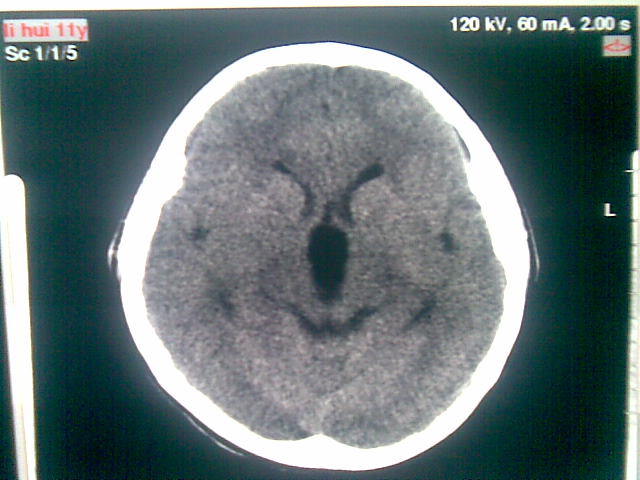

以下是引用随光逐影在2010-1-5 16:32:00的发言:[br]1)鞍上池囊性占位性病变,不排除蛛网膜囊肿可能;建议行mri检查。2)脑积水。

以下是引用yangyang2000在2010-1-5 20:41:00的发言:[br])鞍上池囊性占位性病变,不排除蛛网膜囊肿可能;建议行mri检查。2)脑积水

以下是引用yangyudong333在2010-1-5 21:28:00的发言:[br]1)鞍上池囊性占位性病变,不排除蛛网膜囊肿可能;建议行mri检查。2)脑积水。